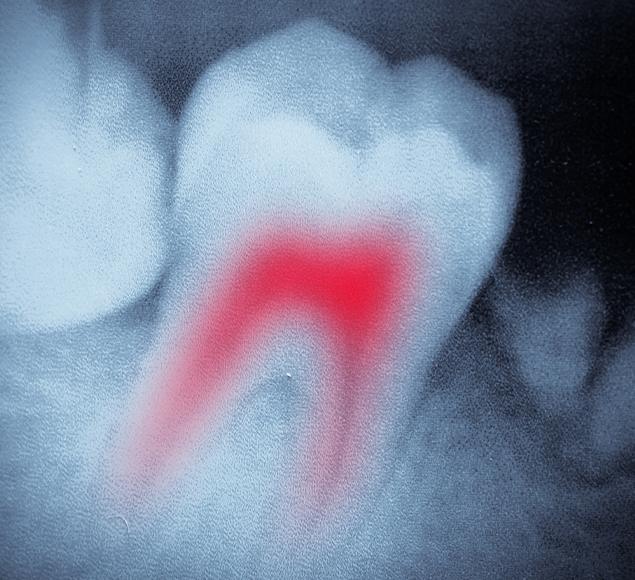

Root canal therapy is an effective way to treat a tooth that has been severely decayed, infected, or damaged. Rather than removing the tooth, the procedure involves carefully cleaning out the infected pulp tissue, disinfecting the inner chamber, and sealing it to prevent further problems. This preserves your natural tooth and avoids the need for extraction.

To protect the tooth after treatment, a custom Dental Crown is often recommended. This restores full function and allows you to eat, speak, and smile comfortably. At RC Dental, we use modern tools and proven techniques to help make the process as smooth and comfortable as possible.